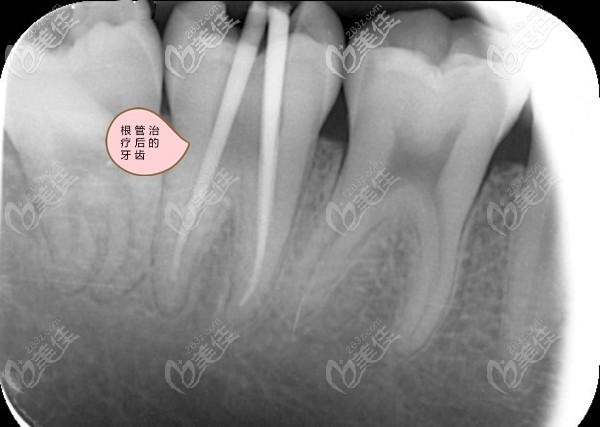

我第6磨牙的牙根弯曲做根管治疗难度大吗?

小区门口这家牙科诊所的医生,说我的牙根弯曲根管治疗通不开,让我去大医院的口腔科治疗,我已经拍了全景片,想请懂行的朋友帮我看看,是不是像我这种牙根弯曲难做根管治疗呀。

事实上,磨牙的牙根80%以上都是弯的,相比直的牙根,治疗起来难度肯定会增加,也很考验医生的经验和技术。好在现在有一种牙科显微镜设备,可以将牙齿的根管放大,还可以对口腔内进行补光,这样大大增加了治疗的便利性,效果也明显提升。

对于弯曲度不是很大的牙根,只要不是狭窄、钙化或是根分叉过多,也都是可以做完善的根管治疗的,做那种显微根管治疗效果相对会更好些,不过,许多小牙科目前都还没有引进这种设备和技术。